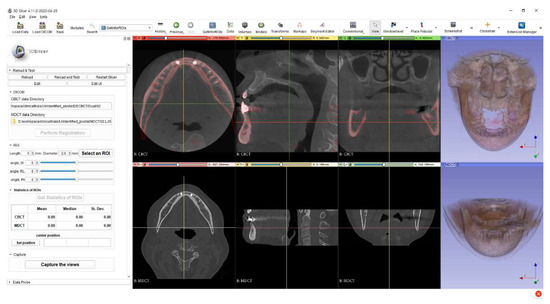

2.3. Software Development to Extract Information of the ROIs